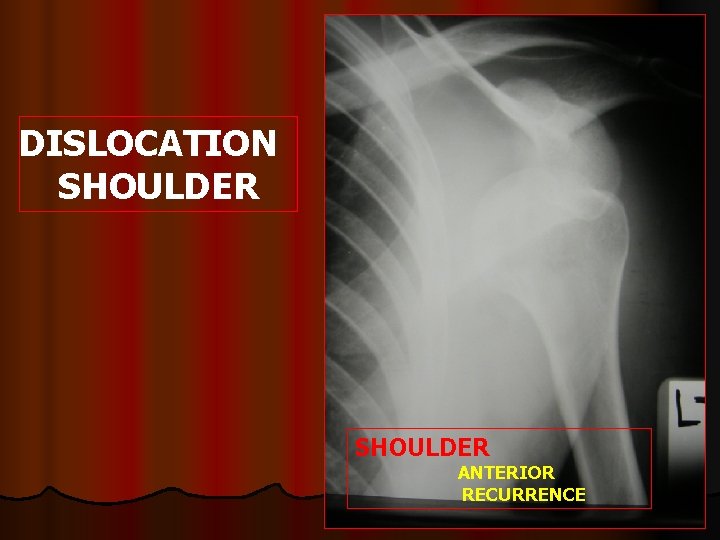

DISLOCATION SHOULDER ANTERIOR RECURRENCE

l Axillary nerve injury Deltoid wasting